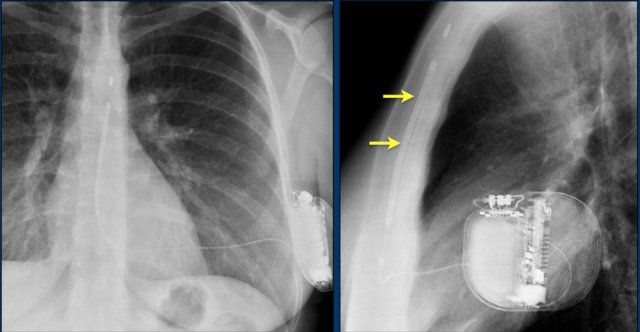

The images show a pacemaker with an atrial and ventricular lead.

The tip of the atrial lead is pointed upward and anteriorly, because the ideal position is in the right atrial appendage, where it is anchored within the coarse trabeculae.

The tip of the ventricular lead is positioned in the apex of the right ventricle, which is located to the left of the spine on a frontal chest X-ray and anteriorly on a lateral view.